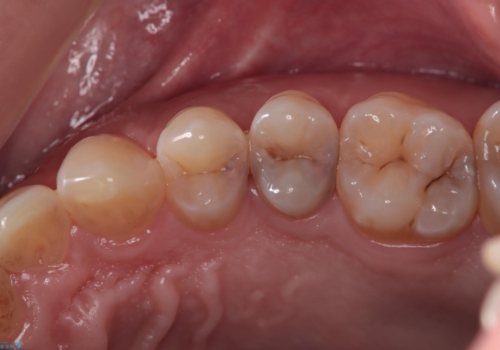

[ オールセラミッククラウン ] すき間の目立つ前歯をきれいにしたい!

担当医 大元洋佑

![[ オールセラミッククラウン ] すき間の目立つ前歯をきれいにしたい!の症例 治療前](https://seimitsushinbi.jp/wp/wp-content/uploads/2024/04/19ba00c303161603f49f83dcced20d62-500x350.jpg?v=1711938361)